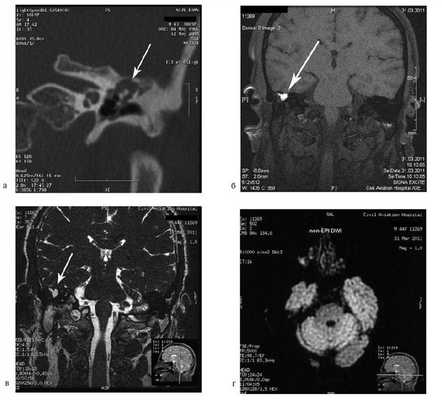

Больная У., 25 лет, обратилась с жалобами на снижение слуха на правое ухо, периодические выделения из правого уха. 18 лет назад была выполнена радикальная операция по поводу острого мастоидита, острого гнойного среднего отита справа. После операции развился парез лицевого нерва. В связи с продолжающимися обострениями через 8 лет была выполнена повторная операция с тимпанопластикой и мастоидопластикой. Частота обострений снизилась, но периодические выделения из уха продолжались. При отомикроскопии визуализируется неомембрана на задней стенке наружного слухового прохода с отверстием 2×4 мм, которое ведет в мастоидальную полость. Дно и стенки полости необозримы.

![]()

На КТ височных костей справа послеоперационная полость, заполненная мягкотканным образованием, определяется большой костный дефект в направлении сигмовидного синуса и мозжечка (рис. 2, а). Рисунок 2. КТ и МРТ височных костей больной У. с хроническим правосторонним средним отитом. Состояние после радикальной операции (1993 г.), санирующей операции с мастоидопластикой и тимпанопластикой (2003 г.). Холестеатома. Парез лицевого нерва. а — КТ; б — МРТ основания черепа в режиме Т1; в — в режиме Т2; г — в режиме non-EPI DWI.

Больной была выполнена МРТ (рис. 2, б—г).

В режимах Т2 и non-EPI DWI определяется сигнал высокой интенсивности, в режиме Т1 — низкоинтенсивный сигнал. Это может свидетельствовать о наличии холестеатомы мастоидальной полости и пирамиды височной кости. Диагноз: хронический правосторонний средний отит; состояние после радикальной операции в 1993 г. и санирующей операции с мастоидопластикой и тимпанопластикой в 2003 г.; холестеатома; парез лицевого нерва.

Больной произведена санирующая реоперация, в ходе которой удалена холестеатома больших размеров, заполняющая отшнурованную послеоперационную полость. Эта полость распространялась до верхушки сосцевидного отростка, граничила с твердой мозговой оболочкой и достигала верхушки пирамиды височной кости. Полость облитерирована. В послеоперационном периоде получен хороший функциональный результат. Ухо толерантно к воде, не было обострений, гноетечения, головокружений. Сохранилась кондуктивная тугоухость I степени. МРТ через 9 мес подтвердила отсутствие холестеатомы.

Больной А., 44 лет, обратился с жалобами на периодические (2 раза в год) гноетечения из правого уха. Ранее пациенту неоднократно предлагалось оперативное вмешательство.

При отомикроскопии определяется утолщение барабанной перепонки, перфорация не визуализируется, признаков холестеатомы нет.

На КТ правой височной кости определяется затемнение в области аттика и антрума, цепь слуховых косточек сохранена (рис. 3, а). Рисунок 3. КТ и МРТ височных костей больного А. с адгезивным средним отитом справа, фиброзной облитерацией аттика. а — КТ; б — МРТ основания черепа в режиме Т1; в — в режиме Т2; г — в режиме non-EPI DWI.

Пациенту выполнена МРТ основания черепа по описанной методике (рис. 3, б—г).

В режиме Т1 и Т2 справа определяется очаг с высокой интенсивностью сигнала, тогда как в режиме non-EPI DWI патологических образований не выявлено. Диагноз: адгезивный средний отит справа, фиброзная облитерация аттика.

В связи с отсутствием данных о холестеатоме операция не производилась, выявленные изменения расценены как фиброзные изменения, оторея была обусловлена периодическим возникновением наружного отита. Больной получал консервативное лечение.